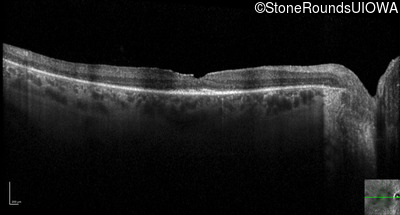

Optical Coherence Tomography - Right - 20/25

Exemplar / OCT Stack